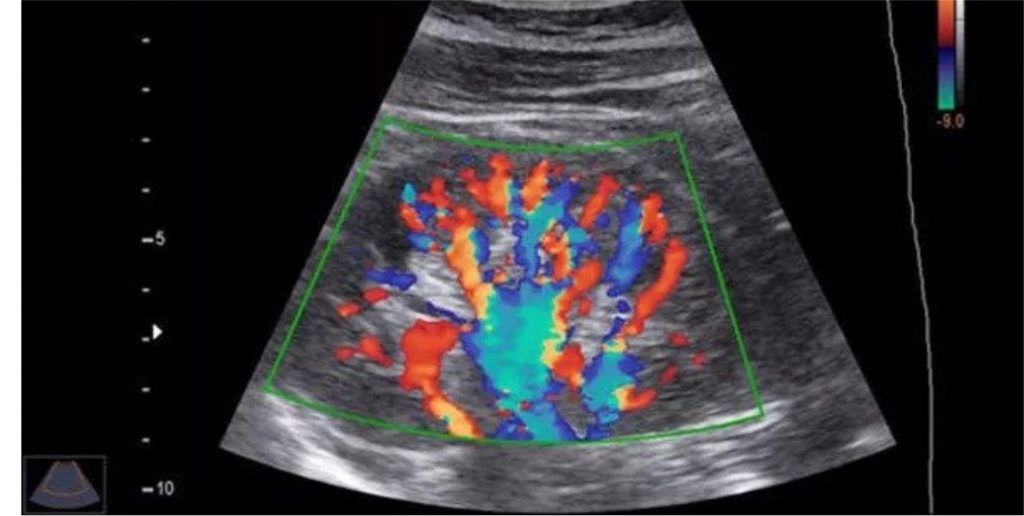

Ureteric stone on ultrasound!KUB ULTRASOUND! HYDRONEPHROURETER! How To Perform Kub Ultrasound When healthcare providers use ultrasound to look at. This blog post aims to provide a. Kub ultrasonography is a diagnostic tool that utilizes sound waves and a computer to generate images of kidneys, ureters and urinary bladder. Read more on the kub. Learn the basics of kidney and bladder ultrasound in just 5 minutes! A kub ultrasound is an examination. How To Perform Kub Ultrasound.